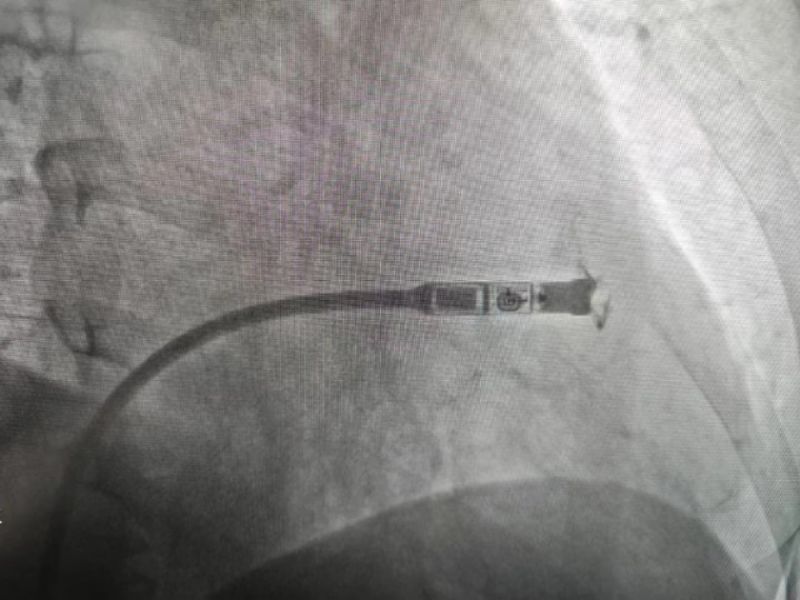

國慶前夕,延安大學(xué)咸陽醫(yī)院心血管內(nèi)科五病區(qū)成功完成了一例Micra雙腔無導(dǎo)線起搏器的植入術(shù),這是延安大學(xué)咸陽醫(yī)院在實(shí)施首例單腔無導(dǎo)線起搏器后,再次完成首例雙腔無導(dǎo)線起搏器(Micra)的植入手術(shù),也是咸陽市首例雙腔無導(dǎo)線起搏器植入術(shù)。此次接受Micra無導(dǎo)線起搏器是延安大學(xué)咸陽醫(yī)院心血管內(nèi)科五病區(qū)患者何大爺(化名),患者15天前出現(xiàn)心悸、氣短,伴短暫性意識障礙,當(dāng)?shù)蒯t(yī)院診斷“急性腦梗死”,因錯過最佳溶栓及取栓時(shí)機(jī),患者出現(xiàn)左側(cè)肢體無力來我院神經(jīng)內(nèi)科就診,于住院第二天,患者再次突發(fā)意識障礙,心電監(jiān)護(hù)最長停搏5秒以上,搶救治療后出現(xiàn)快速型心房顫動及心房撲動,因患者有心臟停搏,發(fā)作心動過速時(shí)應(yīng)用抗心律失常藥物風(fēng)險(xiǎn)太高,給治療造成巨大困難,這嚴(yán)重威脅著患者的進(jìn)一步診療。

經(jīng)心血管病院李陽主任、何克強(qiáng)主治醫(yī)師等仔細(xì)分析病情,充分觀察并排除藥物等影響因素后,最終確定患者為病態(tài)竇房結(jié)綜合征(慢快綜合征),考慮到患者血栓風(fēng)險(xiǎn)較高,傳統(tǒng)起搏器為減少術(shù)中及術(shù)后切口處出血,需停用抗凝藥,該患者停用抗凝藥物會增加患者再發(fā)腦梗死或者腦梗進(jìn)展的風(fēng)險(xiǎn),其次患者后期仍需復(fù)查頭顱MR明確腦梗死恢復(fù)情況,與患者及家屬溝通后選擇安裝無需停用抗凝藥物及術(shù)后可行核磁共振檢查的雙腔無導(dǎo)線永久起搏器。

手術(shù)過程:經(jīng)過充分的術(shù)前討論,在延安大學(xué)咸陽醫(yī)院心血管病院吳棟梁院長、劉雄濤副院長的指導(dǎo)與支持下,李陽教授、何克強(qiáng)主治醫(yī)師、辛浩主治醫(yī)師與導(dǎo)管室介入團(tuán)隊(duì)的共同努力下,經(jīng)過超聲科、心電中心等多學(xué)科協(xié)作,成功為患者植入雙腔無導(dǎo)線永久起搏器,術(shù)后第二天患者在起搏器保障下經(jīng)藥物治療恢復(fù)正常的竇性心律。目前患者心臟情況及腦梗均恢復(fù)良好,已順利出院。

科普:Micra無導(dǎo)線起搏器號稱“世界最小起搏器”,無需植入心內(nèi)膜導(dǎo)線,也無需在胸前皮下制作囊袋放置脈沖發(fā)生器(起搏器),手術(shù)僅需局部麻醉,通過股靜脈穿刺,將起搏器經(jīng)導(dǎo)管植入心腔內(nèi),手術(shù)時(shí)間短,減少出血、血腫及感染風(fēng)險(xiǎn),術(shù)后恢復(fù)快,肢體活動不受限,無異物感。

優(yōu)勢:比傳統(tǒng)起搏器體積減少93%,體積更小,重量僅2g,類似一顆維生素膠囊;雖體積只有傳統(tǒng)起搏器十分之一,但其小小身體儲存大能量,續(xù)航時(shí)間超過12年,整個手術(shù)過程平均約30分鐘,植入成功率高,術(shù)后8-12小時(shí)即可下床活動,術(shù)后1-2天即可出院;兼容1.5T(特斯拉)/3.0T全身核磁共振掃描。滿足患者植入Micra之后疾病的診斷和治療需求。